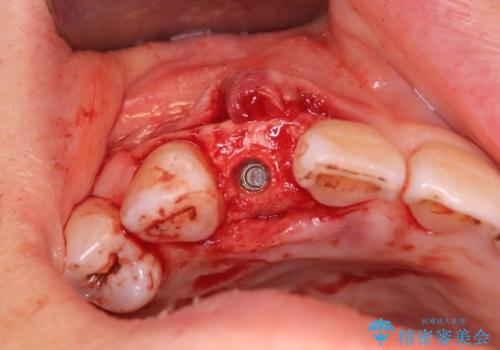

さらに、インプラント治療を併用することで、失われた歯の機能を取り戻し、より自然で健康的な見た目を実現します。インプラントは、人工の歯根を顎の骨に埋め込み、その上に歯の形をした人工歯を装着する治療法で、ブリッジや入れ歯に比べて違和感が少なく、しっかりとした咀嚼力を取り戻すことが可能です。

インプラント治療の利点としては、以下のような点が挙げられます:

•自然な見た目と感触:本物の歯とほとんど区別がつかない見た目と感触を提供します。

•長期的な解決策:適切なケアを行うことで、長期間にわたって使用することができます。

•顎骨の健康維持:インプラントが骨に埋め込まれるため、骨の減少を防ぎ、顎骨の健康を維持するのに役立ちます。